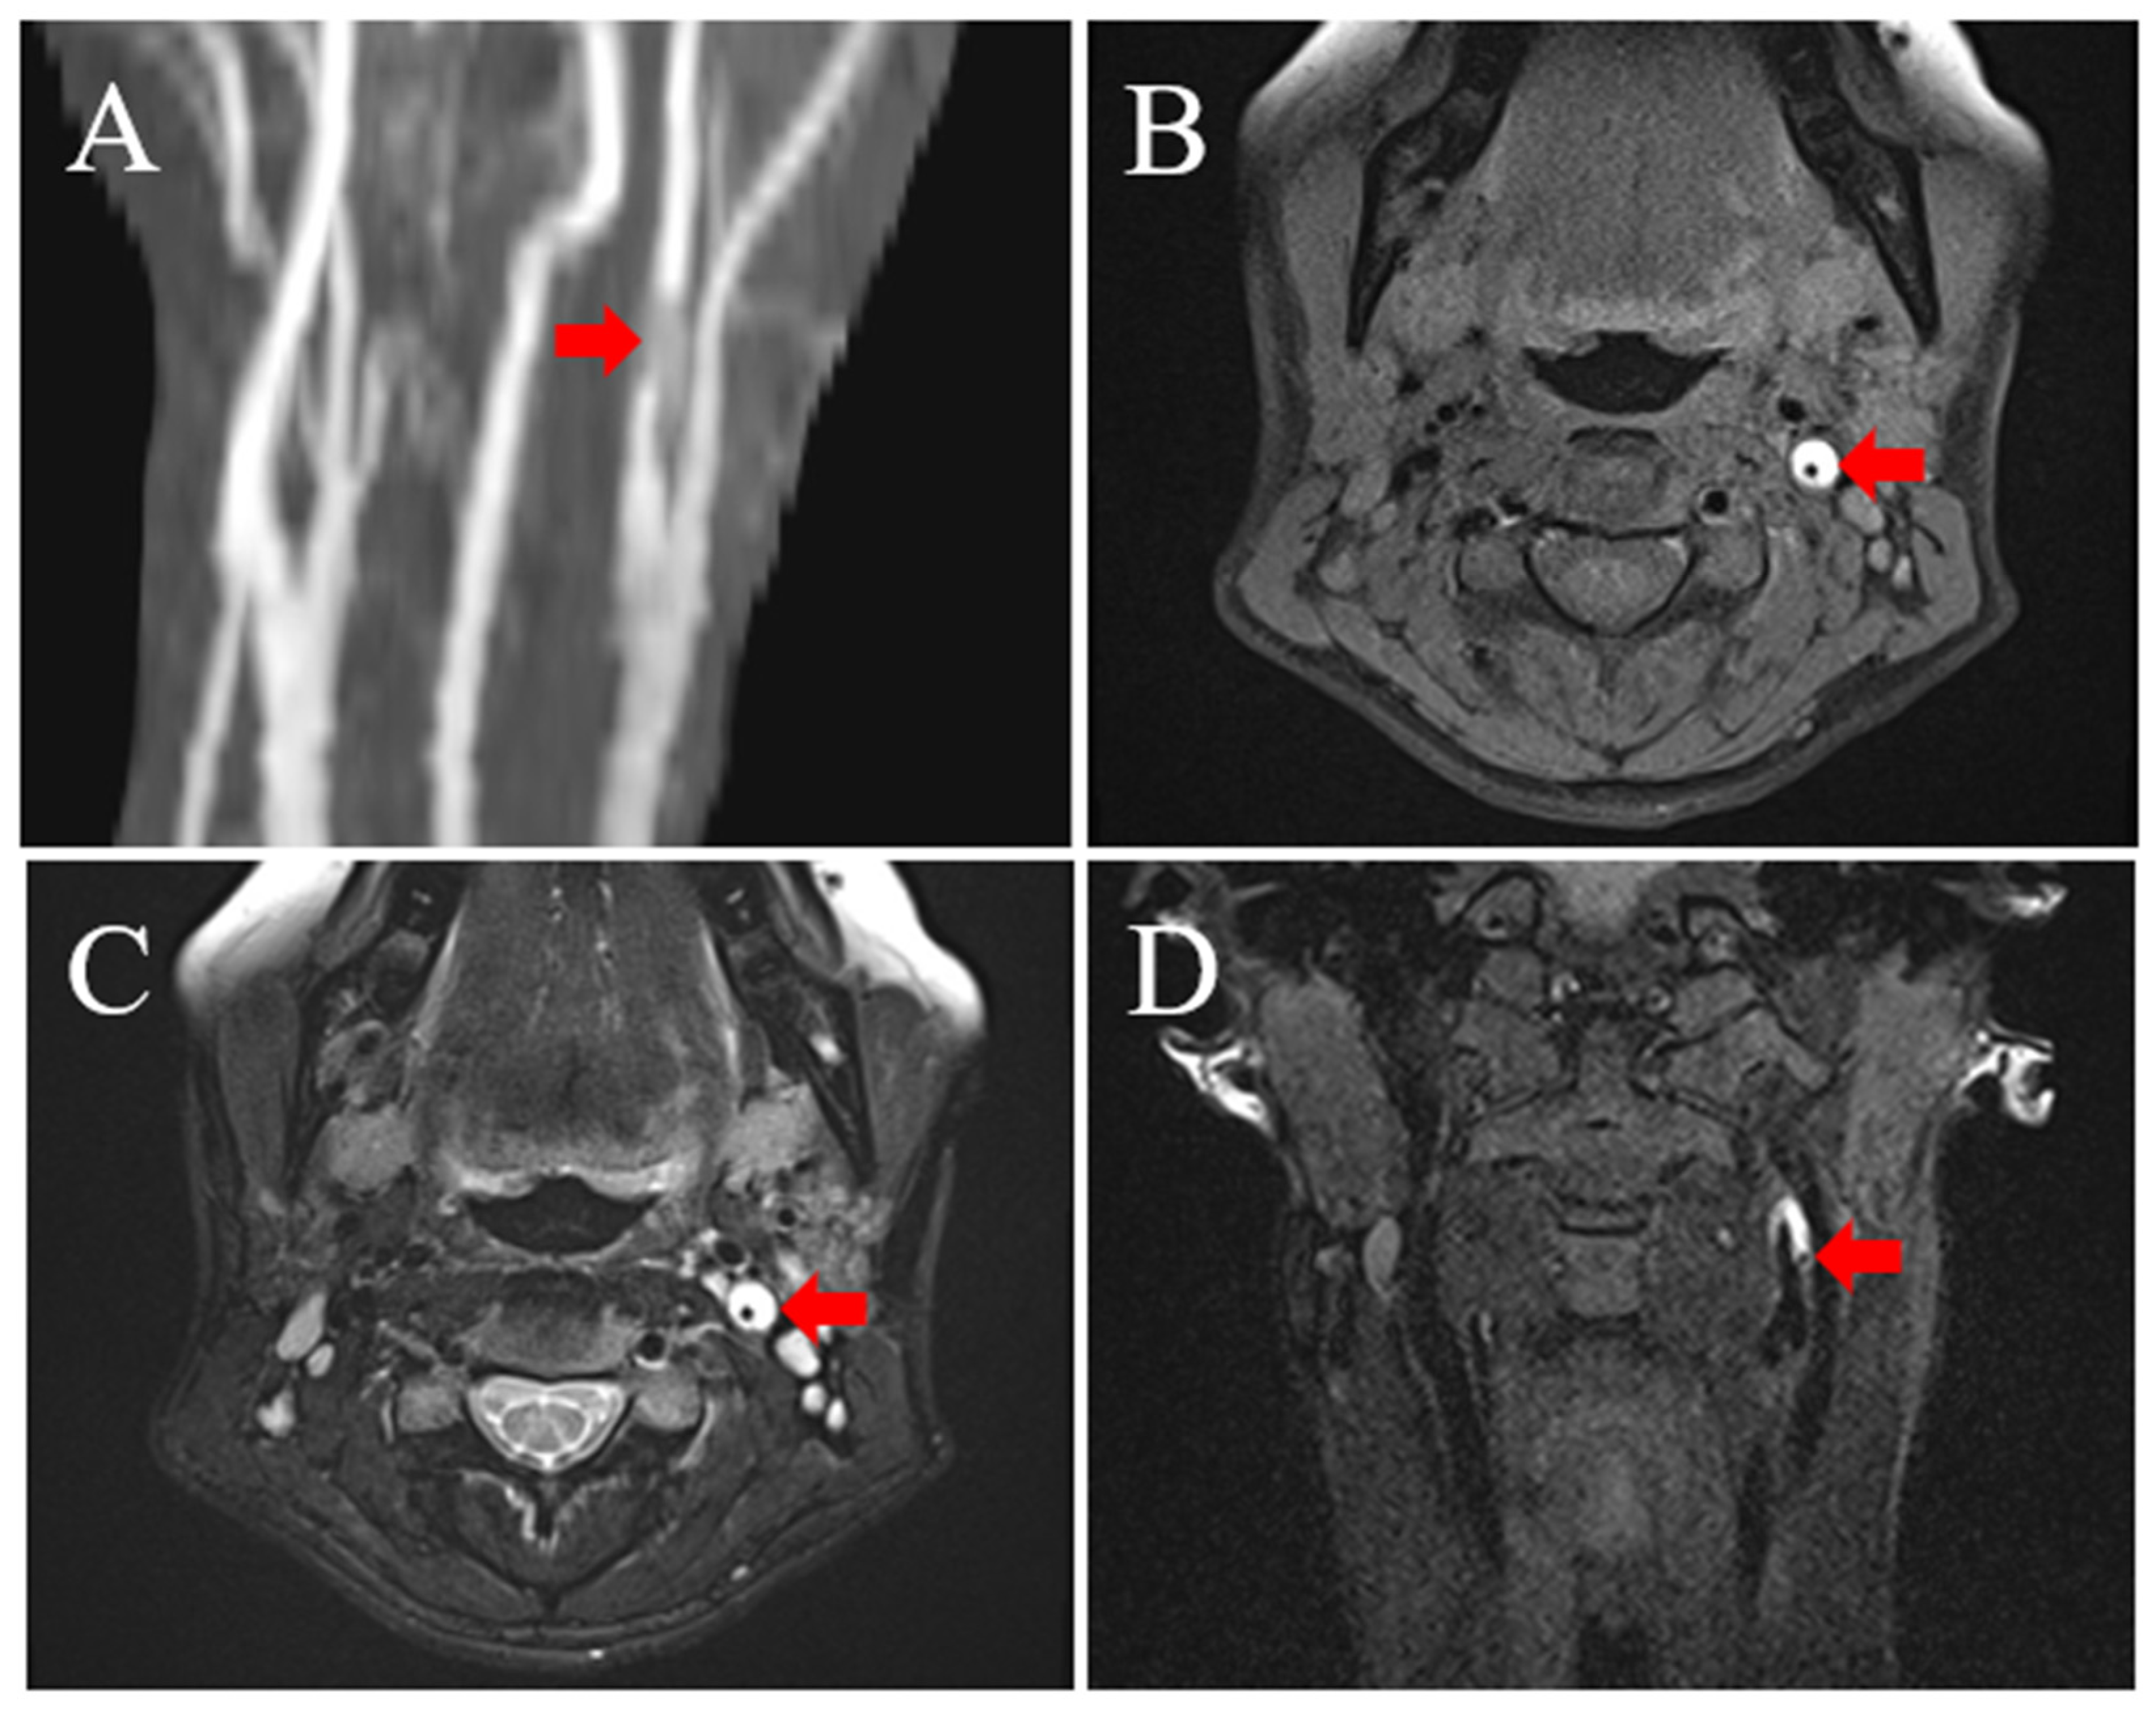

2. Illustrative Case